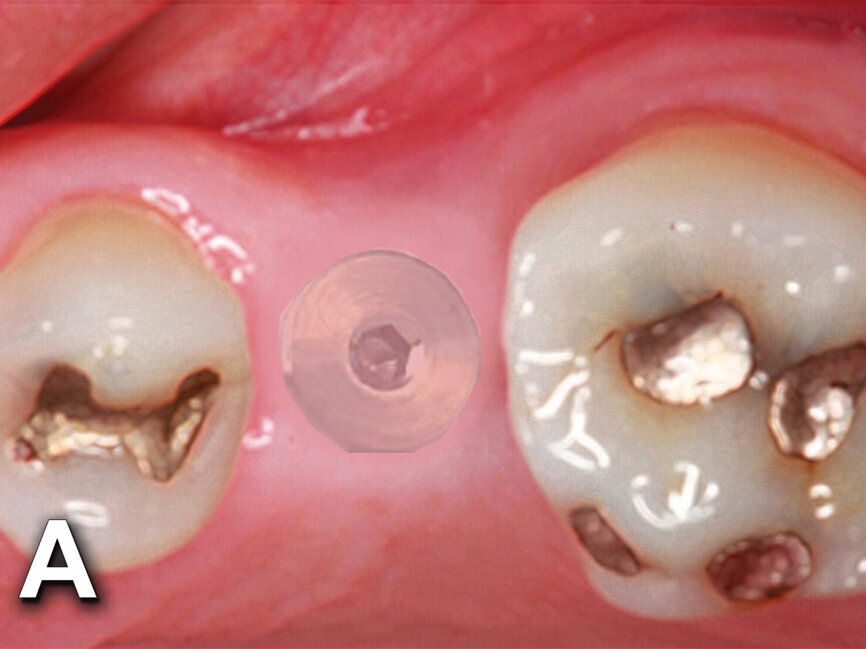

Figs. 4a: Implant to be uncovered (4a) presents with two options depending on width of attached gingiva available. Wide band of attached gingiva will remain after removal of tissue over cover screw, and the diode is utilized in a spiral pattern starting at center until fully exposed (4b). With the narrow band of attached gingiva present, an elliptical cut is made with the diode and tissue is pushed buccally and lingually to preserve the attached gingiva (4c). (Photo provided by Dr. Gregori M. Kurtzman)

Fig. 4b: Implant to be uncovered (4a) presents with two options depending on width of attached gingiva available. Wide band of attached gingiva will remain after removal of tissue over cover screw, and the diode is utilized in a spiral pattern starting at center until fully exposed (4b). With the narrow band of attached gingiva present, an elliptical cut is made with the diode and tissue is pushed buccally and lingually to preserve the attached gingiva (4c). (Photo provided by Dr. Gregori M. Kurtzman)

The width of attached gingiva remaining will dictate the best method for implant uncovery (Fig. 4a). When a wide band of attached gingiva is present and a sufficient amount (3 mm or greater) will be present after uncovery on both the buccal and lingual, then the diode laser is activated and inserted at the center of the site and worked in a spiral pattern outward until the entire cover screw is exposed (Fig. 4b).